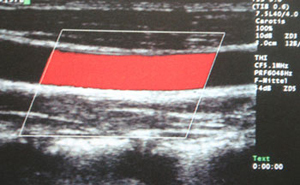

Ultraschallbild (Duplexsonographie):

verengte Schlagader